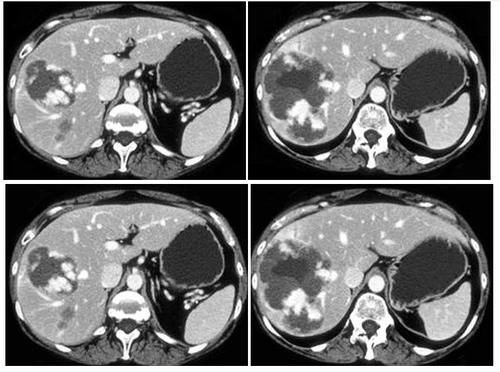

首先,复发和转移是癌症最本质的特征,因为一旦出现复发和转移,往往意味着随后的病情进展会以极快的速度发展,病人的预后会相对较差,也意味着现阶段的治疗手段已经对其失去了作用。

所以,从确诊癌症到临床治愈,这一整个周期中,我们最需要做的就是防治复发和转移。

在所有种类的癌症中,绝大多数的癌症复发和转移高峰期都在5年内,有些是1年内,也有一些癌症是3年内,最为可怕的是半年内,比如90%的三阴性乳腺癌复发转移时间多在术后的1.5~3年,70%的胶质母细胞患者病程约在3-6个月。

【 临床|癌症治疗3阶段,1年,3年,5年都是坎!度过才算“临床治愈”!】因此,半年,1年,3年,5年都是癌症病人应该关注的时间线,每一个都是一道“生死劫”,只有一步步地跨过了,超过5年生存期,并且影像学以及血液等各项检查指标稳定或正常,才算达到“临床治愈”的标准。